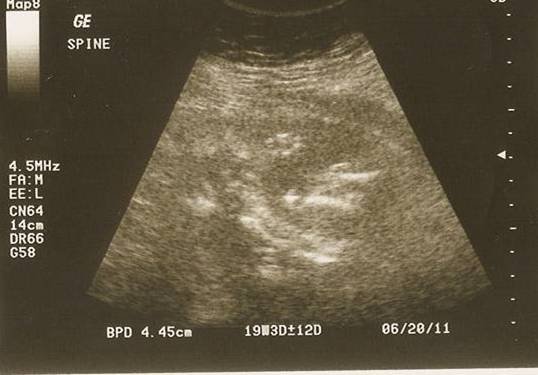

Her spine; I couldn't see it at first but now that I've studied it (yes, studied it!) I think you can faintly see a profile of her head with her thumb up to her mouth. That's what I'm going with anyway - makes me like the picture more! Hehe...